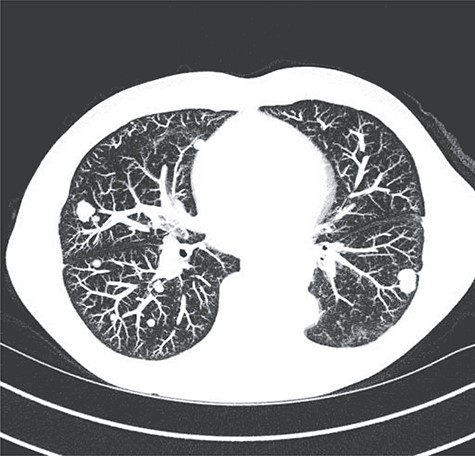

Surveillance scans were negative until 9 months later when multiple bilateral pulmonary nodules were discovered (Fig. 6). Biopsy of one of the nodules revealed recurrent, metastatic disease. He was treated with pembrolizumab for three cycles but had progression. He was then switched to gemcitabine and docetaxel for three cycles but had progression. Most recently, he underwent six cycles of doxorubicin, which showed stable disease.